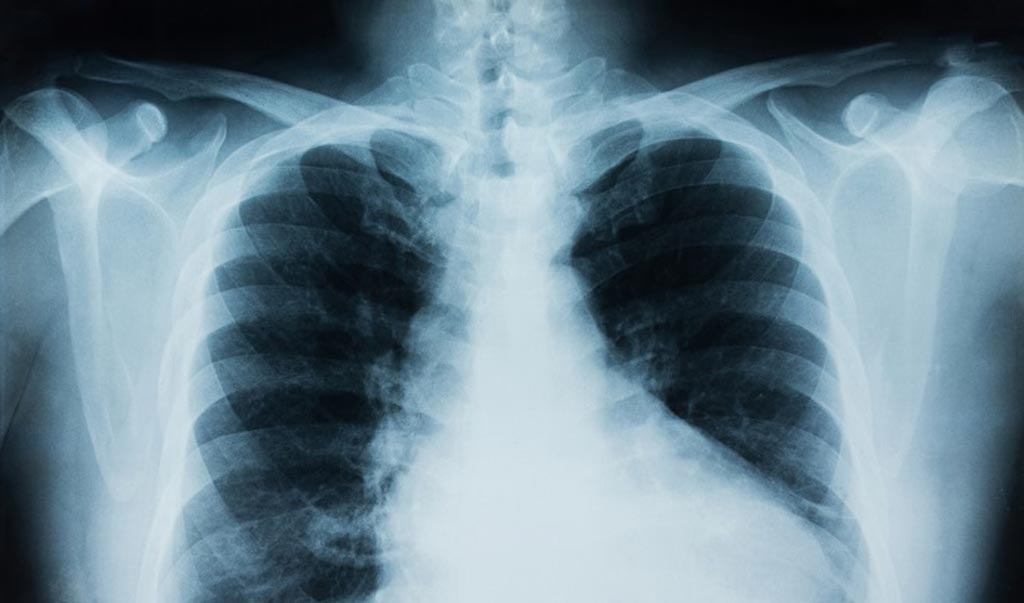

Foto: Twitter

La respuesta a la siguiente pregunta es claramente no. La radiación de cada radiografía es diferente ya que existen diferentes tipos de prueba.

No contiene la misma radiación un TAC de cabeza, que una mamografía, por ejemplo. Cuanta más radiación más peligro conlleva.